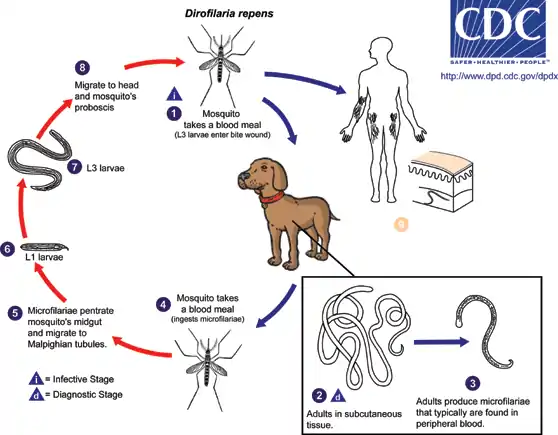

Lifecycle

The lifecycle of D. repens consists of five larval stages in a vertebral host and an arthropod (mosquito) intermediate host and vector. In the first stage, mated adult female worms produce thousands of microfilariae (larvae) into the circulation daily, which are ingested by mosquitoes in a blood meal. Larvae develop into infective larvae within the mosquito over the next 10–16 days, depending on environmental conditions, before being reintroduced back into a new host.[2] Microfilariae undergo secondary developmental changes in the insect. For the final two stages of development, third-stage larvae are inoculated back into a vertebral host during an act of feeding. The adults of D. repens reside in the subcutaneous tissues of dogs and cats, where they mature in 6–7 months. Adult worms are 1–2 mm in diameter (females are 25–30 cm in length, the males being shorter).

Humans are accidental hosts because adult worms cannot reach maturity in the heart or in the skin. Most infective larvae introduced into humans are thought to die; therefore, infected individuals usually are not microfilaremic. Human disease is amicrofilaremic.